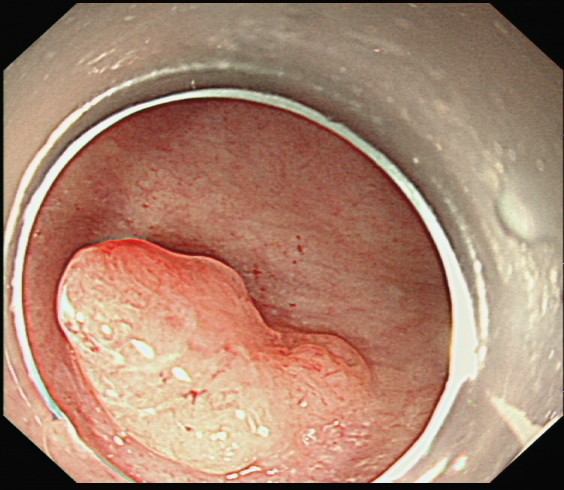

黄女士(化名)近一年来时常感到腹胀,近两周又出现了便血症状。她前往湖北科技学院附属第二医院消化内科就诊,行肠镜检查发现距肛门缘5厘米处有一个直肠息肉,怀疑早期癌变。

消化内科团队为其行进一步超声内镜评估显示,病灶尚未侵及肌层,符合内镜下黏膜下剥离术(ESD)指征。

微创“拆弹”:内镜下的精准手术——ESD